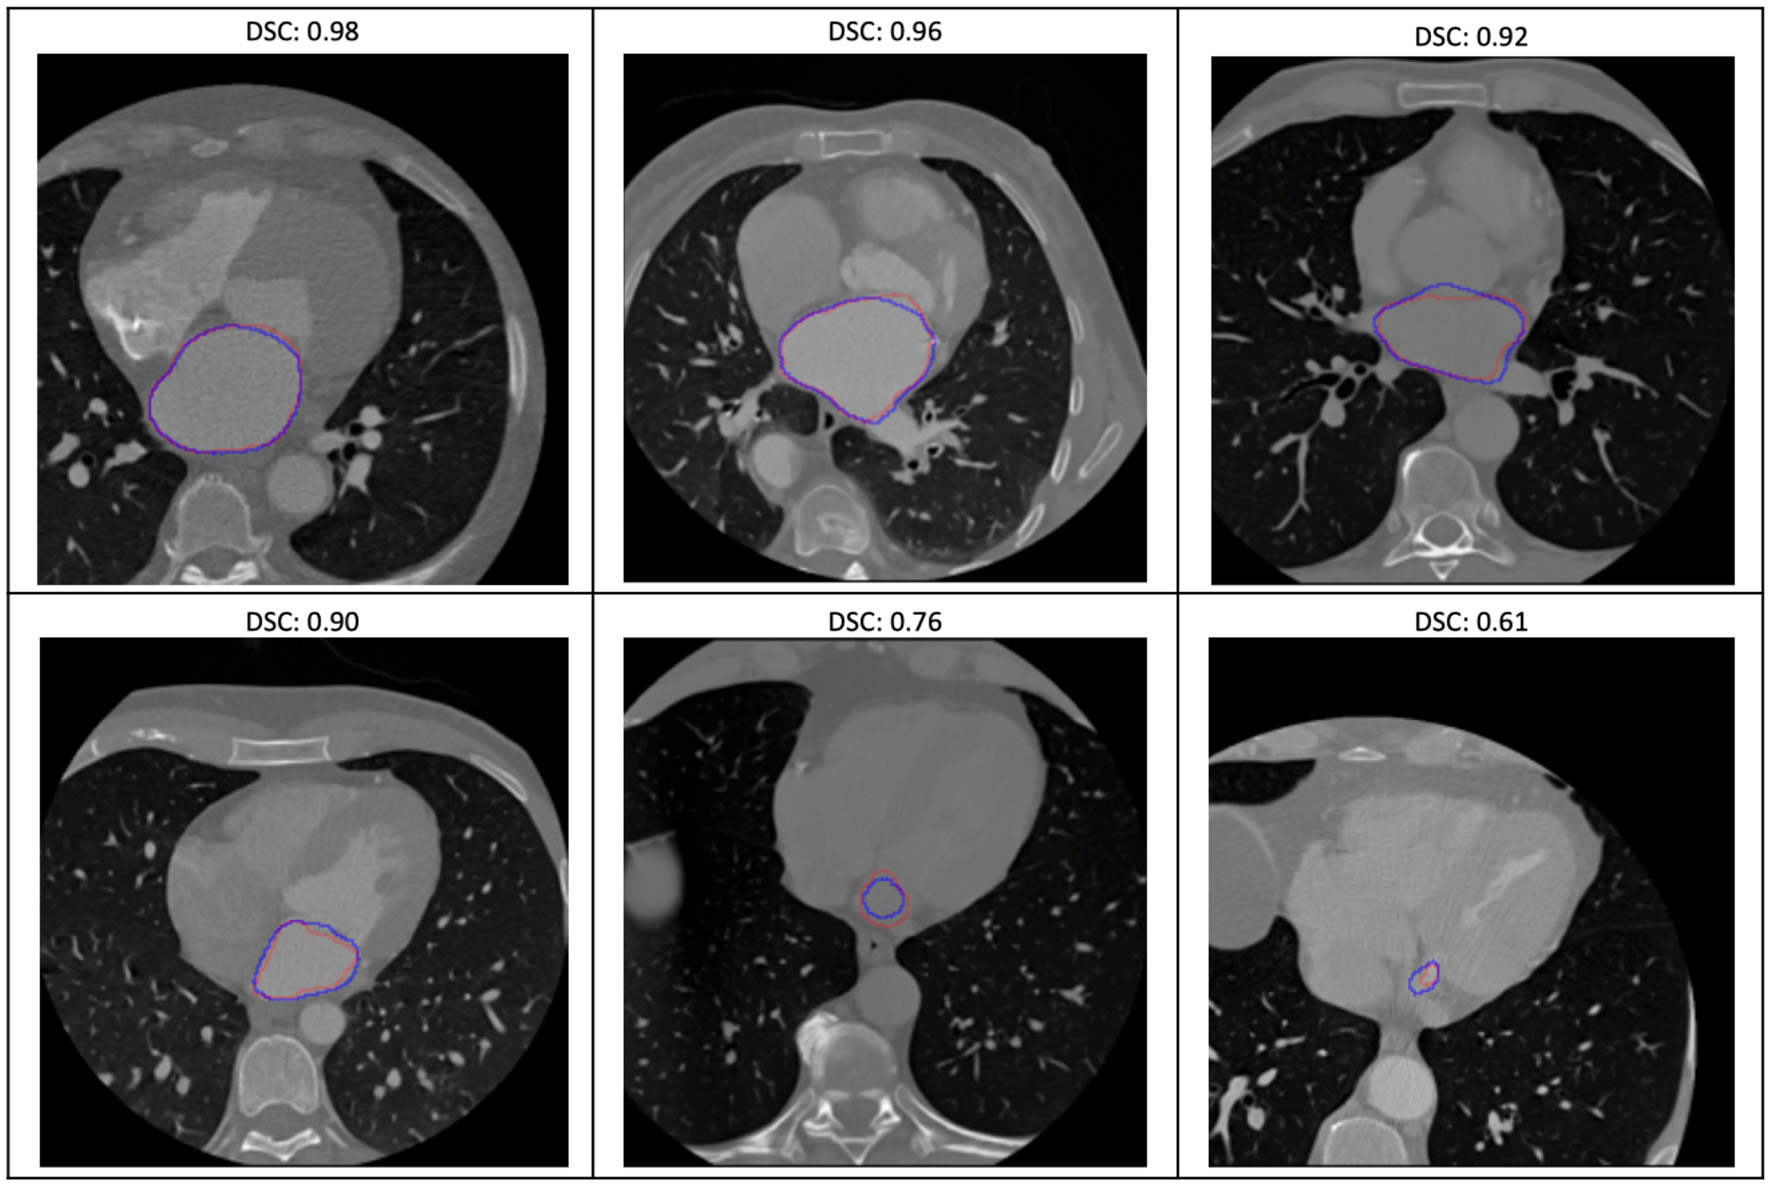

Image Segmentation Model With Quality Assessment

The evaluation of the predicted results of the UNet model was performed using the DSC score, a measure of similarity between the label and predicted segmentation masks, as the performance metric. For the 1,197 evaluation set, the mean DSC is 0.885 (± 0.12 standard deviation; 25, 50, and 75% percentiles are 0.88, 0.93, and 0.95, respectively; the maximum is 0.98). The distribution of the dice score is given in the histogram and boxplot of Figure 4. Figure 5 displays some examples of the predictions of the segmentation model. Overall, the performance of the segmentation model was good (mean DSC > 0.8).

Figure 5

Some examples of the variable prediction of the segmentation model (the red and blue contours represent the label and prediction and the corresponding dice scores are shown on the top of each image).